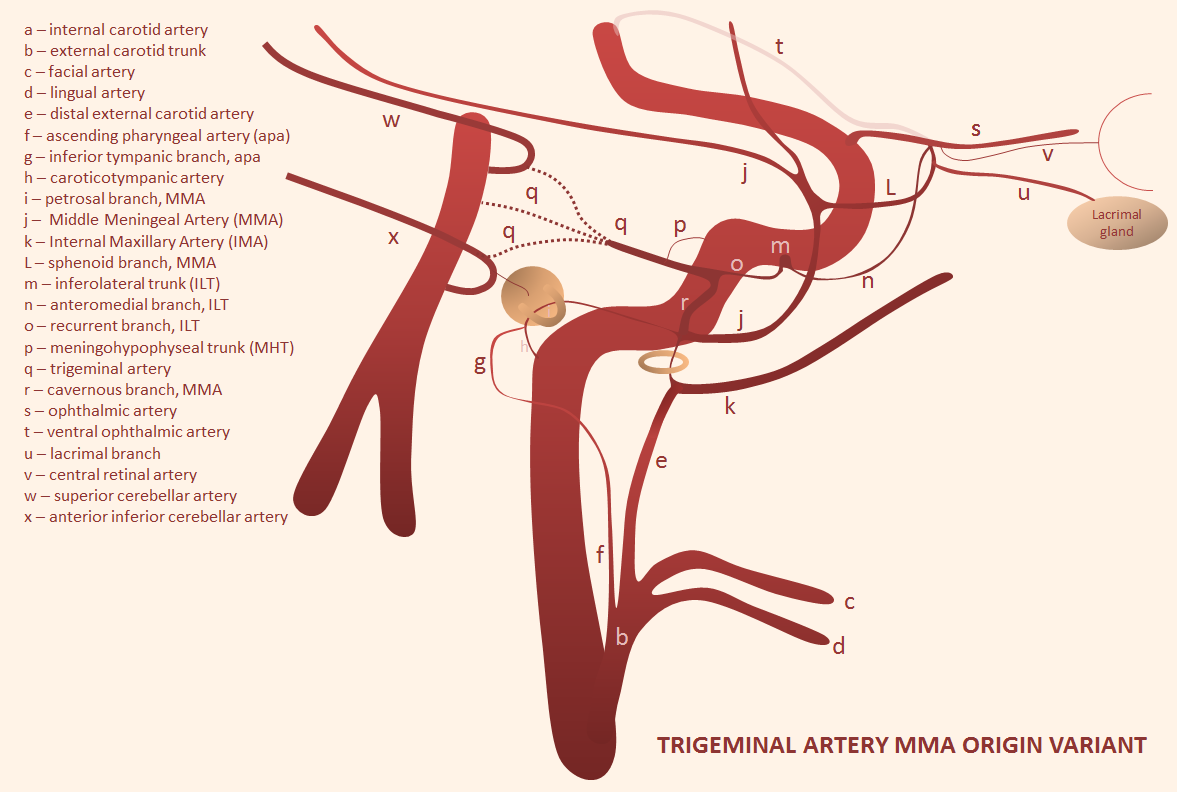

Trigeminal artery origin of the Middle Meningeal Artery — it all makes embryologic sense — check out MMA page